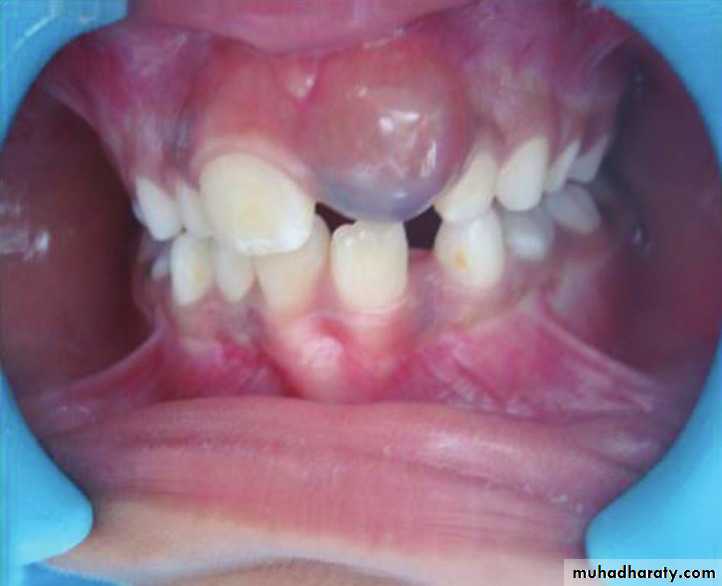

Eruption Cyst

The term eruption cyst is used to describe a dentigerous cyst when it is in the soft tissues overlying the unerupted tooth.• Odontogenic Fibroma

*A 13 year old boy presents with a recurrent friable granular lesion of the anterior maxilla. This is a recurrent lesion after excision.

Differential Diagnosis:

• Pyogenic Granuloma• Peripheral Odontogenic (Ossifying) Fibroma

• Peripheral Giant Cell Granuloma

• Squamous Cell Carcinoma other soft tissue malignancies